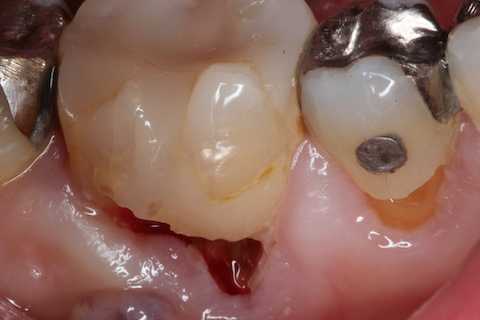

残根上のCR8 2025.10.28